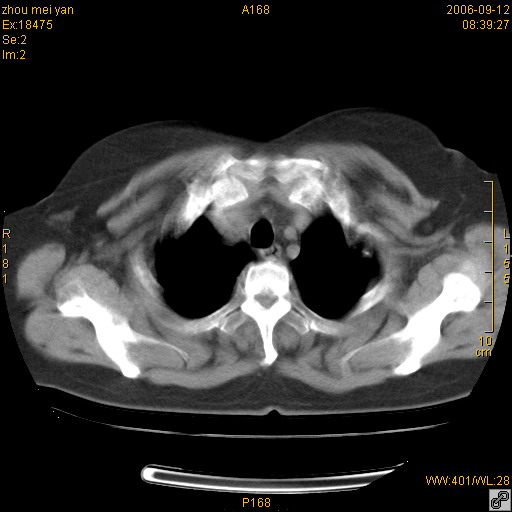

患者、女、55岁。因心率失常住院检查ct发现胸部多发结节。腹部b超肝、胆、胰、脾、肾、子宫附件未见异常。无结核病史,无粉尘接触史。请大家来会诊。谢谢!

胸膜间皮瘤可能性大。在气管隆突前可见一肿大淋巴结影。